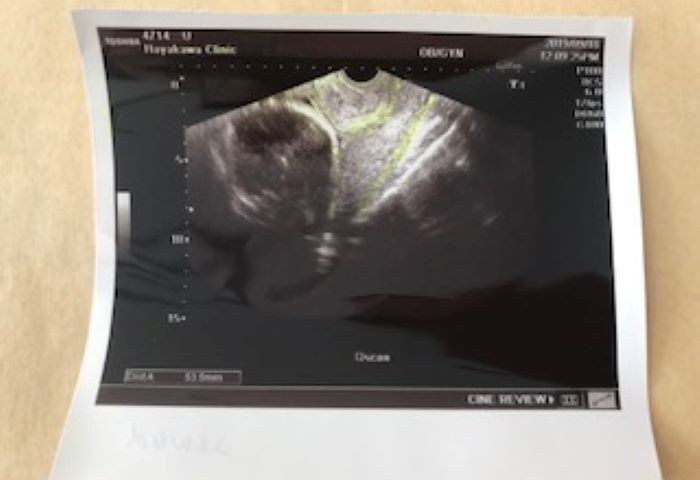

妊娠26週 低置胎盤よ。治ってくれ~

26w4d

妊娠26週目の健診。この日は久しぶりの内診があり、ドキドキしていました。赤ちゃんは元気いっぱいで安心したのですが、胎盤の位置が子宮口に近く、低置胎盤であると告げられました。出産までに胎盤の位置が戻らなければ帝王切開で出産しなければならないこともある、と聞いていた私は、「どうか戻りますように」と、願いました。